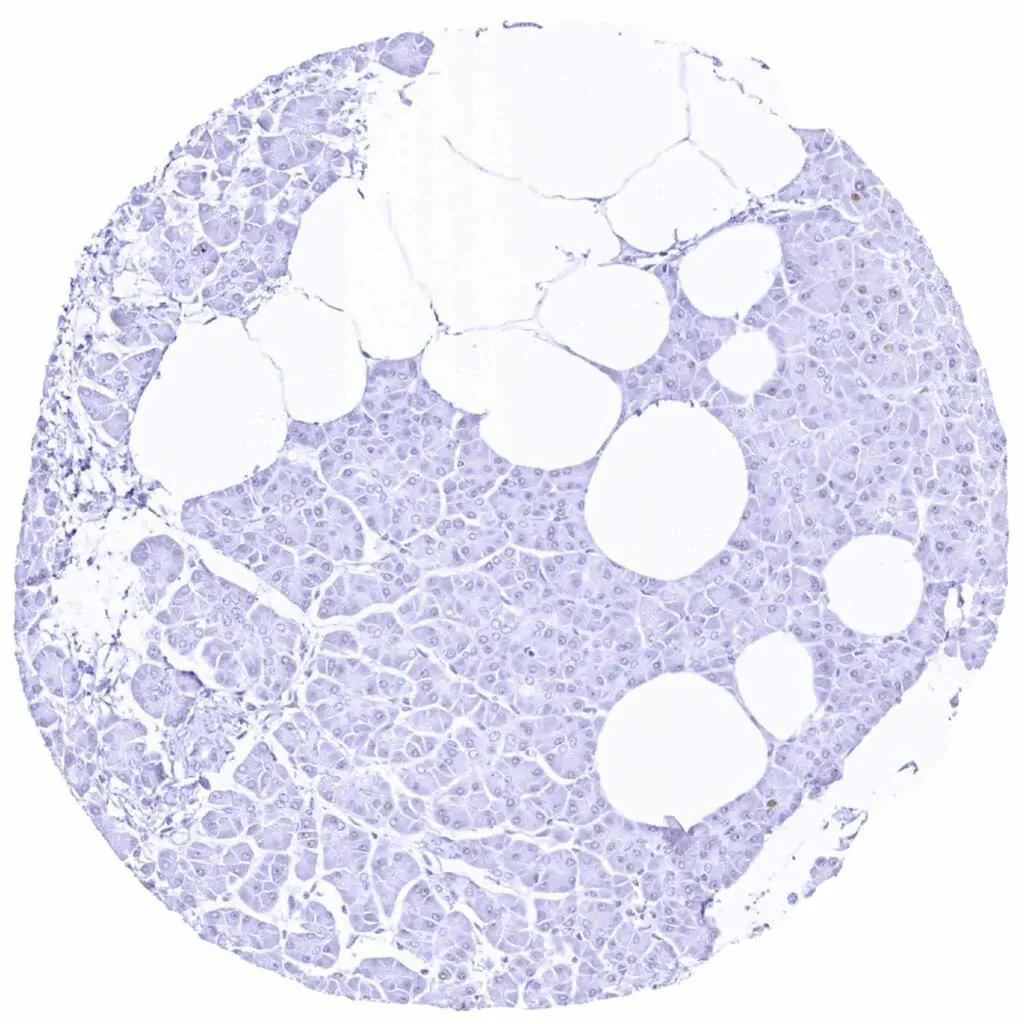

Liver

Pancreas